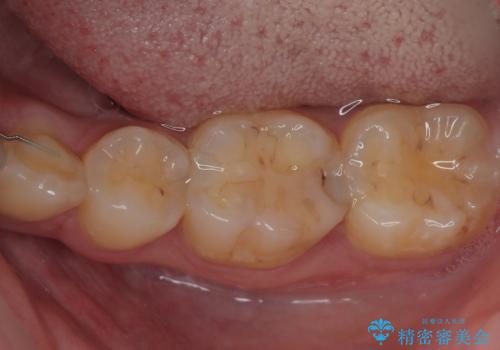

左下にフロスを通すと引っかかる オールセラミッククラウン

担当医 有澤哲郎